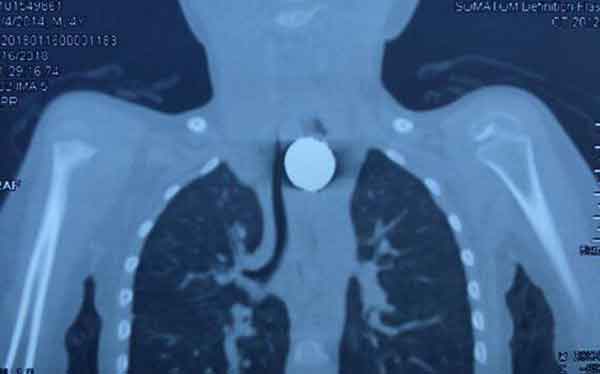

小宝入院后,王洪武立即组织全院包括呼吸内科、胸外科、麻醉科、普外科、耳鼻喉科、儿科等专家紧急会诊,发现患儿食管上段有一圆形异物嵌顿,因此制定了妥善周密的诊疗策略。

接着王洪武改用成人硬质气管镜插入患儿食道内,发现在食管入口三公分处,有一银白色圆形纽扣状异物,并尝试用异物钳、异物篮多次反复调整角度钳取异物,但因异物较大,均未告成功。历经半个多小时紧张的手术,最终王洪武通过硬质异物钳将异物经食管上口取出。手术过程顺利,有惊无险,并未发生大出血及气道撕裂等并发症。